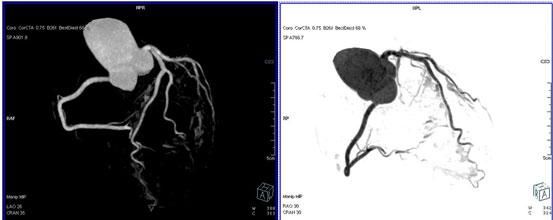

64排螺旋CT冠狀動脈血管成像:

1、簡單:無需經動脈插管,隻需象平時靜脈輸液一樣在肘靜脈内推注相對适量對比劑,然後行快速掃描即可完成整個檢查。

2、安全:64排螺旋CT冠狀動脈造影,對比劑用量較少,無需動脈插入導管,患者無需承擔麻醉及動脈插管等帶來并發症的危險。在冠狀動脈血管疾病的篩查、早期診斷、冠狀動脈成形術和搭橋術前、術後血管評價,冠狀動脈起源異常及心肌橋等方面極具優勢。

3、後處理功能豐富:西門子公司爲SOMATOM Definition AS+ 128層4D螺旋CT配備了功能強大的後處理工作站:MMWP(多産品工作站)和最新型的醫學影像IT工作平台,Syngo.via,智能,便捷。

CT冠脈血管成像:

1.冠脈軟斑塊:

2.混合性斑塊:

3.對于斑塊性質的确定,CT優于DSA: